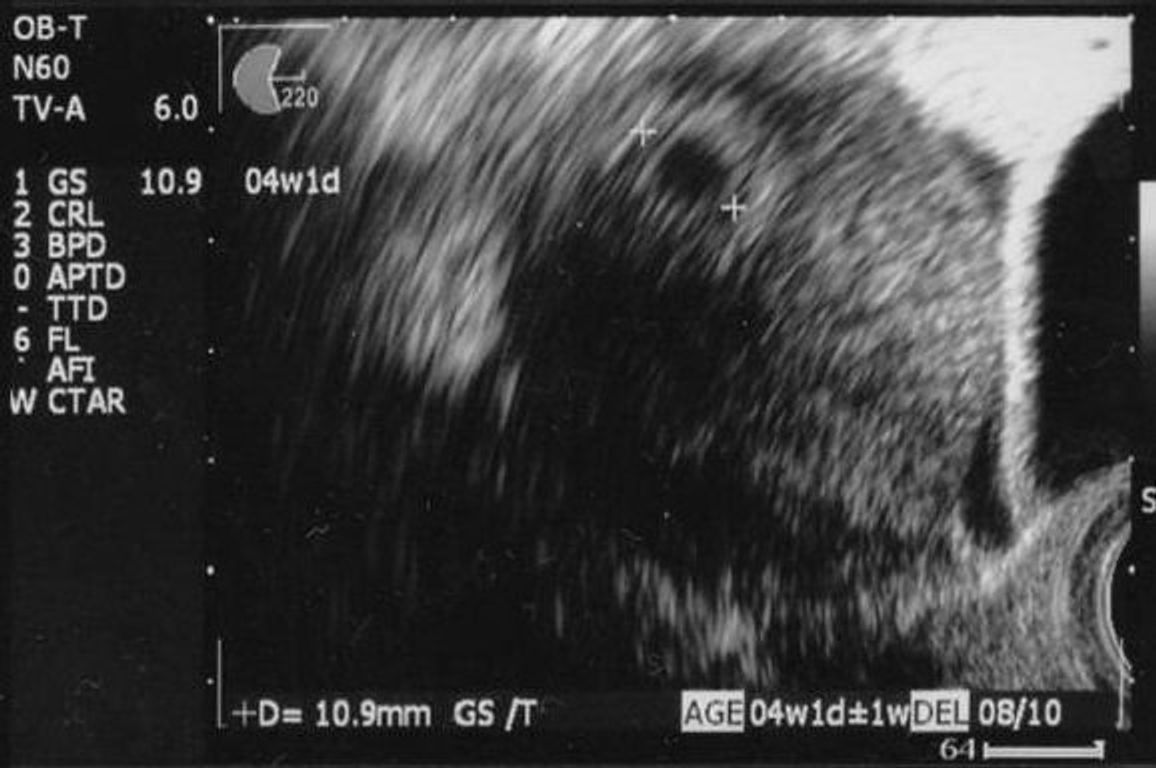

心拍確認は妊娠を確定するのに必要な検査で、通常妊娠5週目から8週目にかけて行われます。 エコー検査で胎嚢や胎芽 (胎児)が確認された後、心拍確認を行うことで妊娠が完全に確定されます。 心拍確認ができれば一安心、とよく言われます。 妊娠6週、7 4W5Dで小さい胎嚢確認。6W2Dでチカチカ動く心 拍確認でしました。私も一緒にドキドキしました。 4w5dで胎嚢確認。5w5dでピピピッと動く心拍確認。 5w4wで胎嚢確認。7w6dで胎芽と心拍確認できまし た! 5W6Dで胎嚢と卵黄嚢確認。

6w3dに心拍確認できる確率と、心拍確認できている人の特徴がわかる 6w3d時点での胎芽の平均的な大きさがわかる 6w3dにエコー検査を受けた妊婦さん60名の、Instagramのアカウントとブログを調査し、統計を取りました。 60名全員の妊娠経過を追っていますので 妊娠検査薬で陽性反応!病院に行ったら胎嚢が確認できなかった 。医師から 「胎嚢が見えない」 「成長速度が遅い」「胎嚢が小さめ」 と言われると不安になりますよね。妊娠初期の心配事の一つ「胎嚢が確認できる時期はいつ?」「目安となる胎嚢の大きさ・平均的な成長スピード」を 心拍確認できるのはいつから? 妊娠5〜6週(生理予定日より2週間以上すぎたあたり) になると、ほとんどの場合で赤ちゃんの心拍が確認できます。 この時期は妊娠2ヶ月あたり「妊娠初期」になります。 赤ちゃんの心拍は、基本的に「超音波検査」で